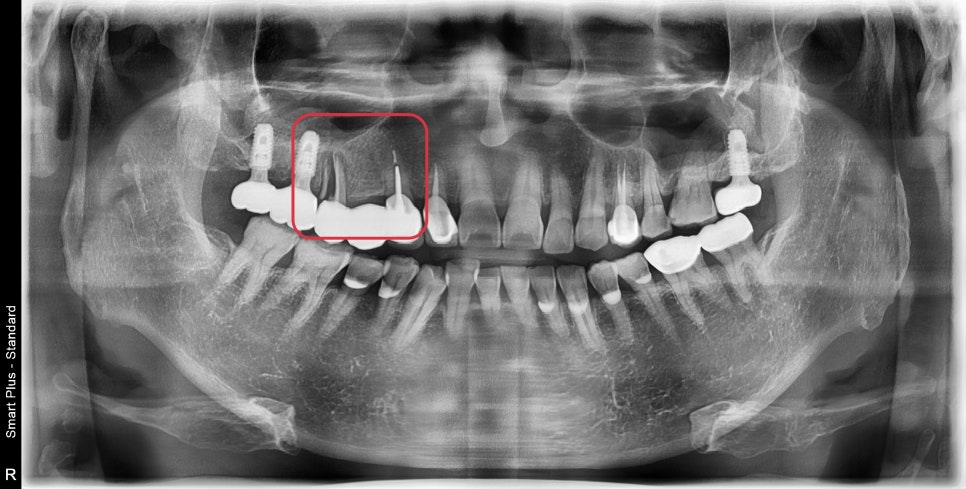

다수의 어금니가 상실된 상태이시고

치주염에 의한 다수의 치아가 흔들리지만

치과 치료에 두려움이 있어서 약을 드시며

버티시다가 도저히 통증이 조절이 안돼 내원해 주셨습니다.

사진에 표시된 부분이 과거에 신경치료가 되어있었고

주변으로 염증이 생겨 치아를 지지해 주는 뼈가 흡수되어

치아 동요도가 관찰되었습니다.